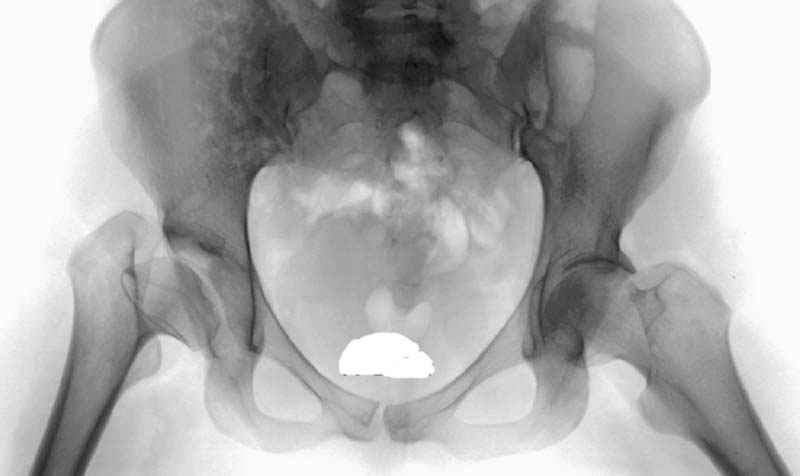

Рис.1 Трехмерная модель тазобедренного сустава с аналогом связки головки бедра. Заметно, что из торца головки выходит капроновый шнур, который с одной стороны прикрепляется к ножке бедренной части модели, а другой его конец, проходя через головку и прикрепляется к вертлужной части модели. Динамометр оказывается не нагруженным, так как аналог связки головки бедра замыкает подвижный узел модели во фронтальной плоскости.

|

Рис.2 Та же трехмерная модель тазобедренного сустава без аналога связки головки бедра. Пружина динамометра удерживает тазовую часть модели от опрокидывания, поддерживая стабильность так же, как отводящие мышцы обеспечивают ее в отсутствии связки головки бедра.